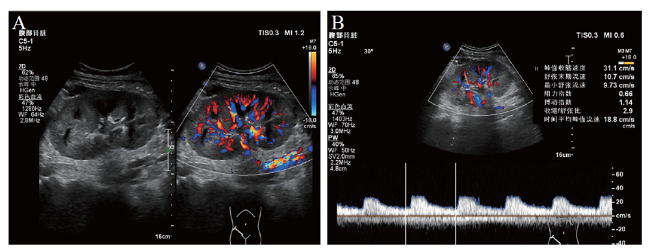

图2 患者术后第16日移植肾彩超检查结果

右髂窝可见移植肾,血流可达被膜下,其中主肾动脉收缩期峰值流速(Vs)0.69 m/s、舒张期末流速(Vd)0.21 m/s、阻力指数0.68,肾段动脉 Vs 0.46 m/s、Vd 0.11 m/s、阻力指数0.66,叶间动脉Vs 0.22 m/s、Vd 0.07 m/s、阻力指数 0.65